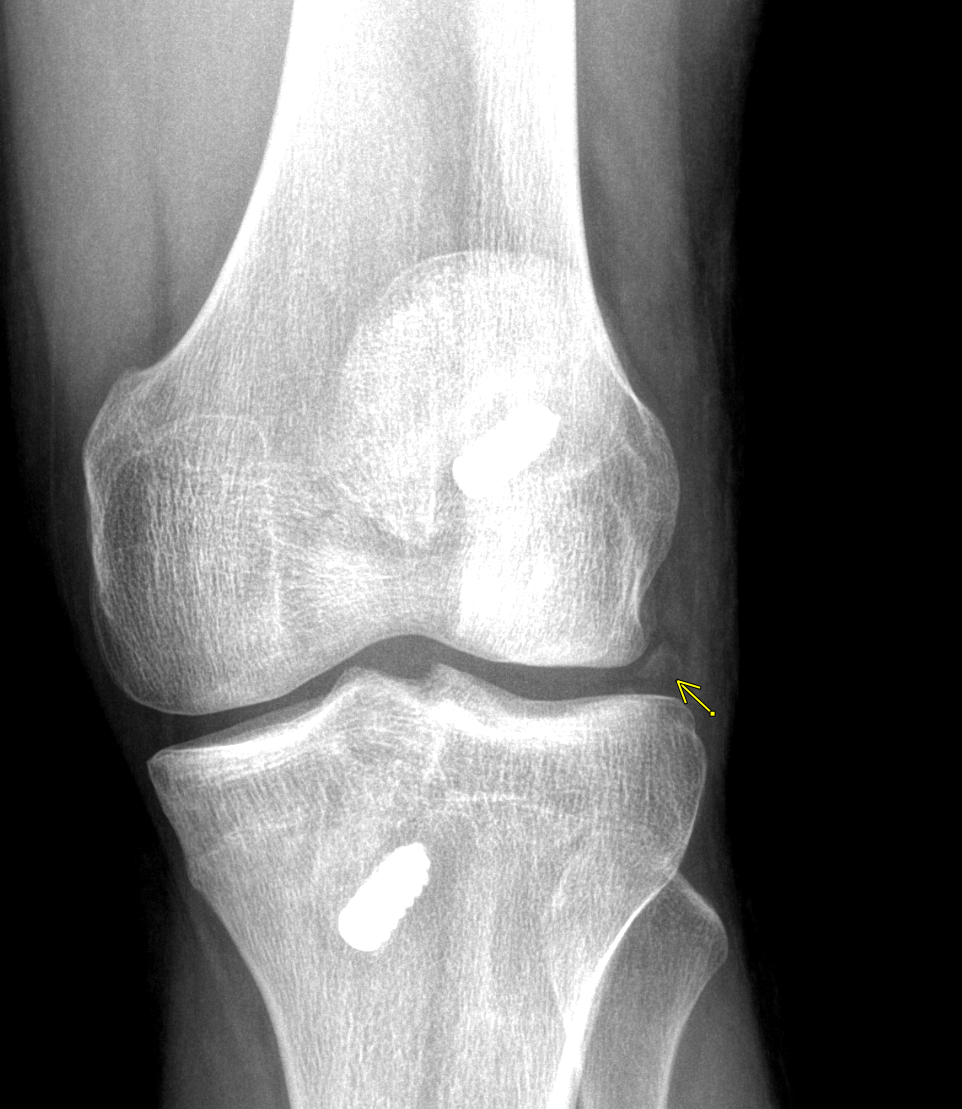

Info Images Findings Impression Reco/Acuity Case Images View Images / Launch Visage Case Notes History 2-month-old presents with decreased right arm movement, increased fussiness, and increased sleepiness for 2 days. Suspected non-accidental trauma. Exam Skeletal survey Prior Study none Dicom View Reference Material

Section 1 Submit Findings CB1550 Findings Skeletal Survey - Technique Check Skull AP/Lat Yes No Cervical and Thoracolumbar spine Yes No Chest X-Ray Yes No Ribs – Left/Right Oblique Yes No Abdominal X-Ray Yes No Pelvis with both hips Yes No Bilateral Humerus, Forearm, Hand Yes No Bilateral Femur, Tibia/fibula, feet Yes No Any additional lateral views of the extremities Yes No The exam is over or under penetrated. Yes No The exam may or may not be limited by overlying structures or soft tissues, body habitus, patient positioning, support devices, or motion. Yes No The area of concern is indicated by the patient, technologist, or care provider. Yes No The area of concern is included on the exam. Yes No Soft Tissues There is soft tissue swelling, indistinctness of fat/muscle planes, gas, or laceration in the area of clinical concern. Yes No There is an effusion, fat pad displacement, or fat fluid level. Yes No There is a radiodense or lucent foreign body. Yes No There are other densities, calcifications, post-surgical changes, or support devices in the soft tissues. Yes No Any support lines/tubes. Yes No Bone There is a break or interruption of the continuity of the cortical or cancellous bone. Yes No There is overriding of the trabeculae with apparent sclerosis. Yes No There is displacement of a fracture fragment. Yes No There is bowing of the bone in addition to the fracture at the apex of the bowed bone concerning for the greenstick. Yes No There is a spiral fracture of the leg concerning for toddler’s fracture. Yes No There is abnormal angulation or bulging of the cortical surface relative to the normal cortex which could be from a buckle or torus fracture. Yes No There is a displaced fragment which may be from avulsion by a tendon, ligament, or joint capsule or from a comminuted or other fracture. Yes No The stress trabeculae or other trabeculae of the cancellous bone are interrupted or otherwise abnormal. Yes No There is subperiosteal or endosteal reaction which could indicate a healing or subacute fracture or other abnormality. Yes No There is hard/soft callus formation. Yes No There is remodeling of the bone. Yes No There is a corner fracture or metaphyseal lesion that could be from nonaccidental trauma. Yes No There are multiple fractures of different ages. Yes No There are vertebral body/spinous process fractures. Yes No There are rib fractures. Location - posterior or lateral. Yes No There is scapular/sternal fracture. Yes No There are fractures of the digits. Yes No There are wormian bones. Yes No There are intrasutural bones. Yes No There is metaphyseal abnormality (lucencies, increased density, erosion) which may be from something other than injury such as stress, metabolic disease (e.g. rickets with loss or distortion of the zone of the provisional calcification), neoplasm (e.g. leukemia), heavy metals, inflammation, or infection. Yes No There are metaphyseal spurs. Yes No There are bony deformities involving multiple bones. Yes No The bones are gracile. Yes No There are non-healing fractures. Yes No There is/are focal or multifocal lytic/lucent, blastic/sclerotic or mixed density lesion(s) or other abnormality. Yes No Overall bone density is increased or decreased with or without thinning or thickening of the cortical or cancellous bone. Yes No Growth plates, ossification centers, apophyses The growth plate(s) is/are abnormal. Yes No There is widening of the physis from a fracture with or without displacement of the epiphysis (Salter-Harris I). Yes No There is a fracture through the physis which then extends into the metaphysis with or without angulation or displacement (S-H II). Yes No There is a fracture through the physis which then extends into the epiphysis and is intra-articular, with or without angulation or displacement (S-H III). Yes No There is a fracture through the metaphysis, physis, and epiphysis which extends into the joint space with or without angulation or displacement (S-H IV). Yes No There is narrowing of the physis from a compression fracture (S-H V). Yes No The apophysis, epicondyle, secondary ossification center, or accessory ossicle is displaced or otherwise abnormal. Yes No The ossification centers are underdeveloped. Yes No Joints and alignment There is an effusion, fat pad displacement, or fat fluid level. Yes No The epiphysis or subchondral bone is fractured, interrupted, flattened, compressed, impacted, displaced, or otherwise abnormal. Yes No There is an intra-articular loose body or chondrocalcinosis. Yes No The joint is widened, narrowed, dislocated, malaligned, or incongruent. Yes No There is pseudoarthrosis. Yes No Other findings There are developmental changes or other anatomic variants or other existing conditions that may or may not be contributing to symptoms which can or should be further evaluated non-emergently or are otherwise incidental. Yes No The remainder of the exam is abnormal for age. Yes No The lungs show focal airspace opacity. Yes No There is pneumothorax. Yes No There is organomegaly. Yes No There is intra-abdominal calcification. Yes No There is displacement of the bowel loops. Yes No There is free intraperitoneal air. Yes No The bowel loops are dilated/obstructed. Yes No There is paraspinal soft tissue abnormality. Yes No